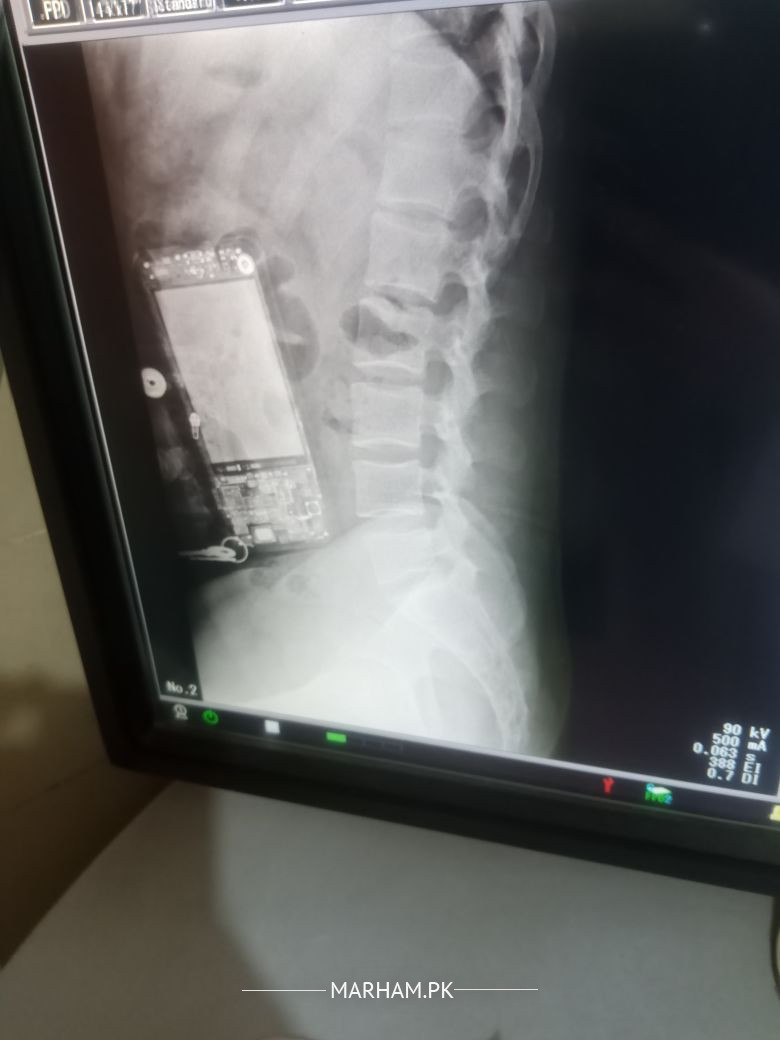

Asking For Self, Male 34, Islamabad

mere back peet pe or pait k sides par pain hota hain x-ray keia Hain result bta den

Looks straightening of spine in lateral view probably due to muscle spasm.

Better to see any orthopedic Surgeon near you for proper assessment and than management

Meanwhile you can take following medicine

Ibuprofen 400mg

one tablet morning and evening after food

Omeprazole 20mg

one tablet at night if you feel heartburn or pain in Stomach